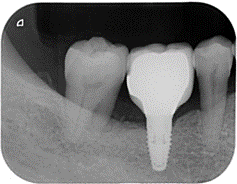

治療後X光

牙齒獲得支撐力,空隙逐漸合起來。